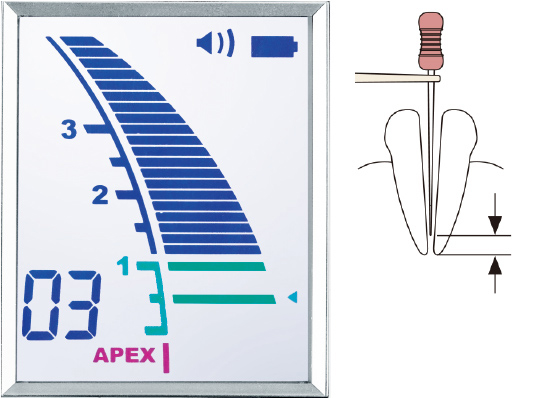

当院で使用している根管長測定器

Root ZX3

根管内の状態に影響されず、高精度な測定を実現します。気温や湿度など環境の変化で生じる誤差を自動補正するキャリブレーション機能を搭載し、常に安定した精度を維持。大きく見やすい液晶画面、リアルタイムで滑らかに動くメーターで快適な操作をサポートし、安全で精密な根管治療に貢献します。

-

ジャスティⅣ

根尖孔までの距離を正確に測るだけでなく、従来は見過ごされがちだった側枝(根の分岐)の検知も可能な高機能測定器です。独自の測定システムが口腔内の環境に影響されない高精度な計測を実現。ファイルの現在位置は3段階で色分けされた大画面に表示されるため、視認性にも優れています。治療の精度と安全性をさらに高め、再発リスクの低減に貢献します。

-

APIT15

2つの周波数におけるインピーダンス差を比較する独自方式で、根尖の位置を正確に検出します。オート/マニュアルの2モードと根管ごとの調整機能で、従来は測定が難しかった多様な症例にも対応。出血がある根管でも測定精度が落ちず、大きくなったアナログメーターが繊細なファイル操作を補助します。